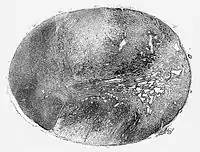

![]() Glioblastoma arising in an astrocytoma. This spinal cord exhibits both a lightly staining microcystic astrocytoma as well as a darkly staining glioblastoma. | |